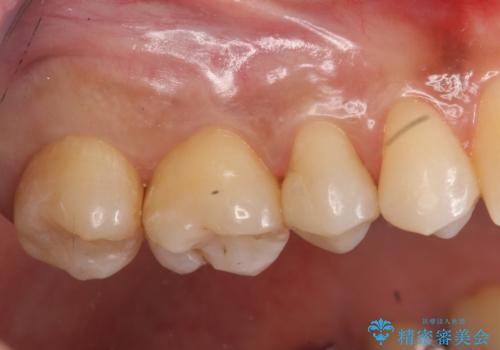

奥歯の虫歯 セラミックインレーに

- 上の奥の虫歯をセラミックインレーで修復しました。

奥歯は力がかかるところであるので、保険適応の白い材料は必ず劣化し、2次う蝕(再度虫歯)になる可能性が非常に高いですので全くおすすめできません。

2次う蝕になり、治療を繰り返していると抜髄(神経を取らないといけない)の可能性が高まります。

特に自費のインレーの適合(歯にぴったり合っている)はとても良く、虫歯になりにくいです。